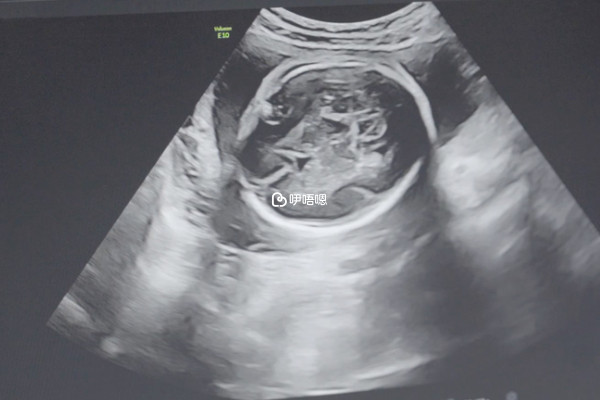

一般來說,在進行試管移植,如鮮胚移植以後,女性需要隨時觀察自身的情況,如果伴有陰道的出血、腹痛等情況,就需要到醫院配合醫生做腹部B超檢查,以診斷是否出現了宮外孕,若是宮外孕需要及時進行處理,以免影響身體健康,反之是可以進行妊娠的。